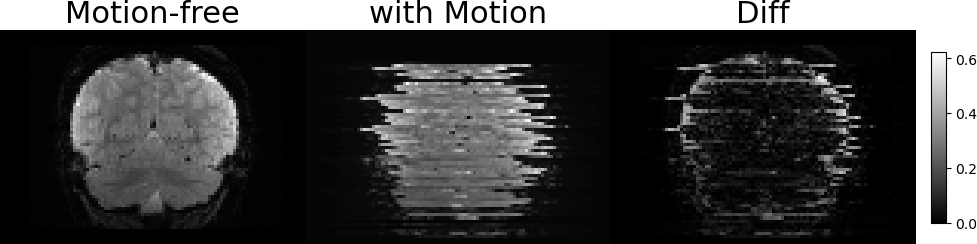

3.2 Representations of Transformations and Slices Generation

Figure 3: Illustration of the SVR problem. Two examples of free-motion volumes and volumes with synthetic motion. From left to right: Coronal LABEL:sub@fig1:a,LABEL:sub@fig1:b and Sagittal LABEL:sub@fig1:c,LABEL:sub@fig1:d views of the free-motion volumes, the generated volumes after applying the rigid transformations and sampling the slices, and the pixel-wise MSE between them, respectively. The artifacts due to the slice-level motion are visible in both Sagittal and Coronal views, however, they are not dipicted in the axial (imaging) axis of the image LABEL:sub@fig1:e,LABEL:sub@fig1:f.